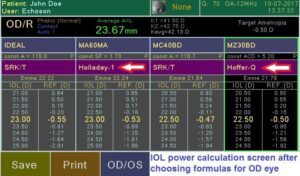

Современный ультразвуковой офтальмологический сканер для визуализации, биометрии и пахиметрии глаза.

Измерение параметров глаза и расчет ИОЛ.

Сенсорный экран (легкое использование благодаря понятному меню, виртуальная клавиатура для ввода данных пациента); внешняя USB клавиатура (опция), цветной 7″ LCD экран, 800×480 пикселей; десять (10) профилей пользователя; запись изображений на внешний USB накопитель; встроенный термопринтер; легкое обновление программного обеспечения через USB порт; USB порт для внешнего лазерного принтера; 6 типов отчета.